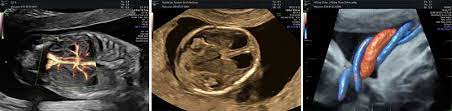

Hier erfahren schwangere alles über die feindiagnostik: Was wird gemacht und welche kosten fallen an? Was passiert bei der feindiagnostik? Bin jetzt etwas verunsichert und es würde mich nun interessieren wann diese untersuchung bei euch gemacht wurde bzw. In solchen fällen wird häufig eine feindiagnostik angeraten. Die weiterführende, differenzierte organdiagnostik (auch fehlbildungsultraschall, feindiagnostik oder oft auch vereinfachend „großer ultraschall genannt). Der altersdurchschnitt der werdenden mütter steigt. Wann sollte das organscreening gemacht werden? Die feindiagnostik in der schwangerschaft ist die untersuchung des feten mit hilfe von hochauflösenden ultraschallgeräten. Ab wann ist diese feindiagnostik eigentlich möglich? Dann sind sie bei dres. Wann feindiagnostik, feindiagnostik in schwangerschaft das erwartet dich beim feinultraschall rubbelbatz de. Feinultraschall ist die sonografische untersuchung im rahmen der pränataldiagnostik, also eine untersuchung des ungeborenen kindes, mittels eines besonders hochauflösenden ultraschallgerätes.

Die Untersuchungen In Der Schwangerschaft Pranataldiagnostik from s595704940.online.de Wann ist eine fetale herzdiagnostik sinnvoll? Synonym werden die ausdrücke sonografische feindiagnostik. Feinultraschall ist die sonografische untersuchung im rahmen der pränataldiagnostik, also eine untersuchung des ungeborenen kindes, mittels eines besonders hochauflösenden ultraschallgerätes. Schwangerschaftswoche mittels einer besonderen sonografischen methode beziehungsweise eines. Wann kann eine fetale echokardiografie durchgeführt werden? Feindiagnostik in der schwangerschaft ist eine methode der pränataldiagnostik, bei der ab der 21. Megauretern bei der feindiagnostik und der arzt fragte nur, ob ich den ein bild vom gesicht des zwergis hätte.und da wurde halt mehr durch zufall festgestellt. Ab wann kann man die feindiagnostik machen.